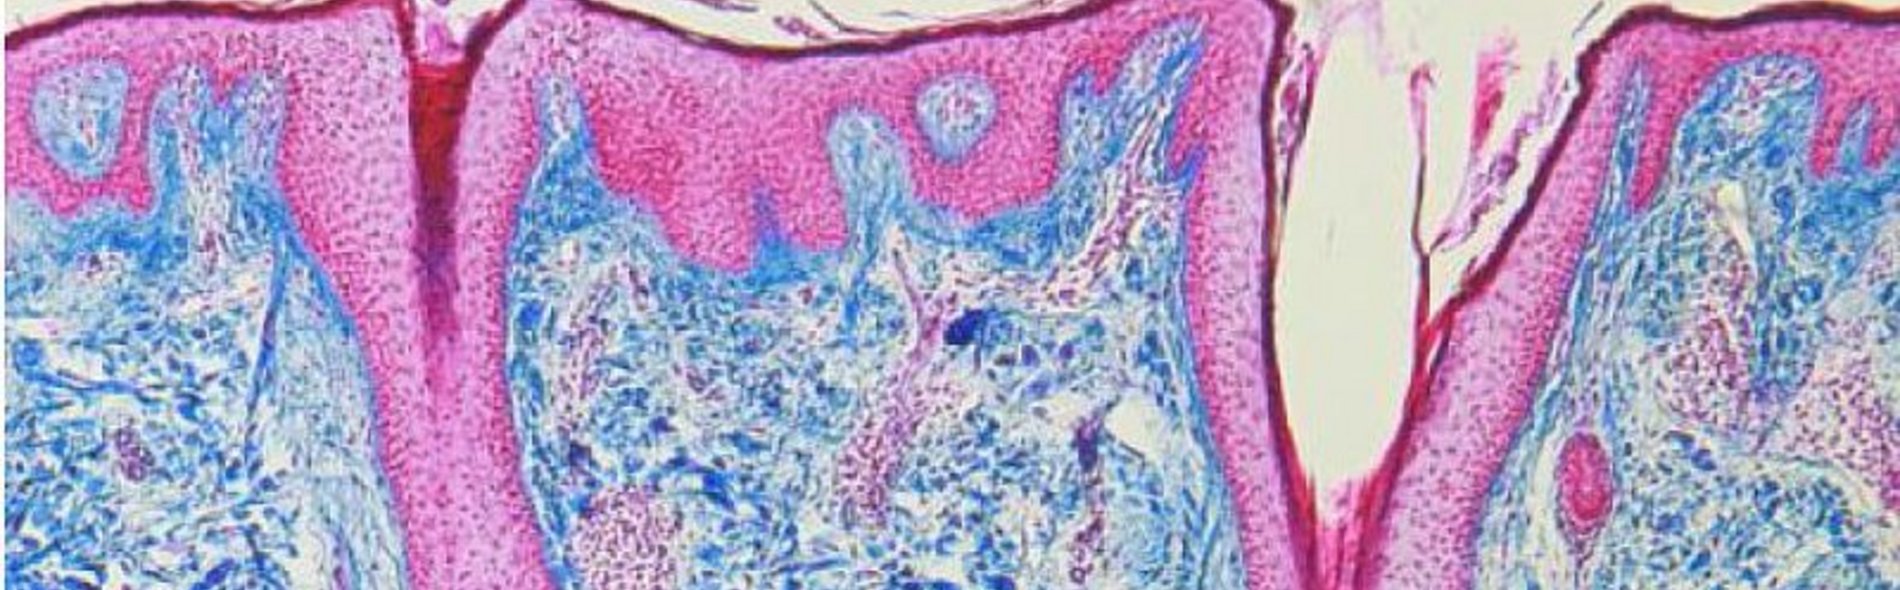

Der Pathologe untersucht Aufbau und Funktion von Organen, Geweben und Zellen um Krankheitsursachen (Ätiologie) und Entstehungsmechanismen (Pathogenese) zu verstehen und den weiteren Krankheitsverlauf, mögliche Therapieansätze und die Prognose zu ermitteln. Die am MVZ Institut Pathologie Offenbach untersuchten Proben sind vielfältig und umfassen große Operationspräparate ganzer Organe oder Organteile sowie winzige Gewebeproben (Biopsien) oder Zellausstriche (Zytologie). Nach Aufarbeitung der Gewebe in den Laboren wird der mikroskopische (feingewebliche) Befund durch den Pathologen erstellt und dient als Grundlage der Therapieplanung für den behandelnden klinischen Kollegen.

Die Ergebnisse seiner mikroskopischen Untersuchungen sind elementare Bestandteile der klinischen Diagnostik und Therapieplanung: jede Karzinomdiagnose wird durch einen Pathologen gestellt. Die Beurteilungen von Vorsorgeuntersuchungen wie gynäkologische Abstriche, Mammographiescreening- oder Koloskopiebiopsien erfolgen durch den Pathologen. Zudem nimmt die Pathologie einen hohen Stellenwert in der Qualitätssicherung im Gesundheitswesen ein.